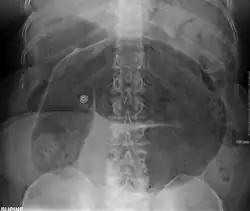

-

Coffee bean sign in a person with sigmoid volvulus -